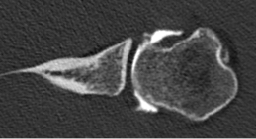

Computed Tomography (CT) Scan

Computed tomography (CT) scans also help the physicians to analyze the bony morphology of the shoulder joint. Before operative management, it is effectively imperative to assess for abnormalities in glenoid version (mean, 4.9 degrees in normal shoulders)[20] according to the Friedman technique,[21] posterior glenoid rim fractures or bone loss, and reverse Malgaigne (Hill-Sachs) lesions. These factors help determining the treatment strategies.